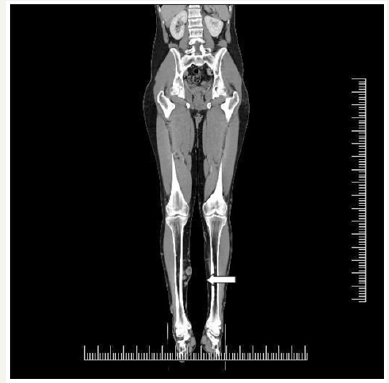

Subsequently, due to suspected Klippel-Trenaunay syndrome, the ultrasound and CT AG examinations of the venous system of lower limbs was supplemented. The CT AG examination shows potential A-V malformation on the lower limb in the anteromedial region of the shin, and varicose focuses throughout the whole tibia (Figure 4). The examination does not confirm any lytic changes of bone structures. The patient was also examined in the respect of haemo-coagulation, and the thrombophilia was confirmed. After diagnostics and preparation, the patient underwent an operation. The stem insufficiency VSM sin.l towards to v. accesoria anterior l.sin., confirmed by ultrasound and CT AG findings were the indication for surgery. Subsequently, crossectomia and stripping VSM throughout the whole course, obliterated vv. perforantes CI-CIII, posterior gastrocnomic and anterior lateral branch. Post operation the patient was afebrile, pressure and pulse stable and compensated, surgical wounds were calm, did not leak healed p.p.i. The patient was informed on the next treatment procedure (elastic bandage, drinking and motion regimen), and was released to the outdoor care.

Figure 4:Varicosity of the right tibia in the transversal section.